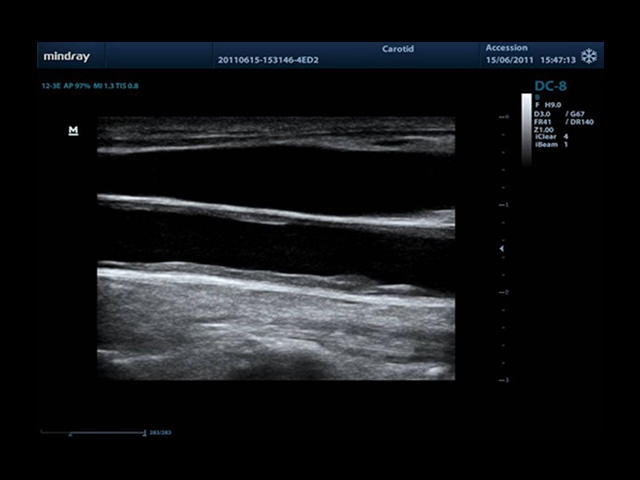

• Auto IMT Package - измерения и анализ толщины комплекса интима-медиа (КИМ) сонной артерии.

• Vascular package - предустановленные параметры, аннотации, маркеры, программы измерений для ангиологии, включая транскраниальные исследования